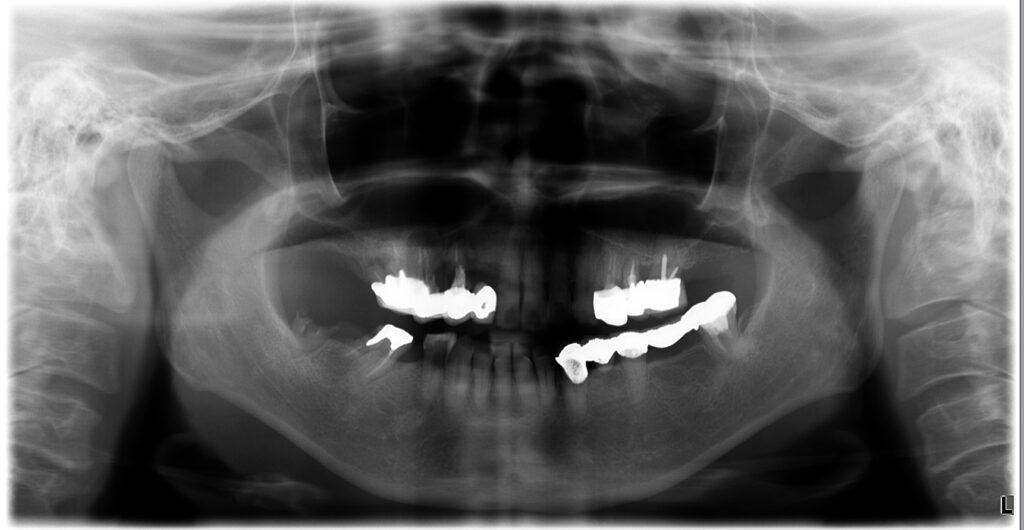

当院では、インプラント本数を絞って上下ともにブリッジ設計とし、さらに部分矯正で前歯の噛み合わせを作り直すことで、少ない本数でも成立するように調整。

結果として、抜歯即時で“オペ1回”で完結させた症例です。

- 上下ともにインプラントブリッジで噛める機能を回復

- 患者様の希望に合わせ、外科は抜歯即時で1回にまとめた

治療の工夫②:上下ともにインプラントブリッジで機能を回復

上下ともにブリッジ設計とすることで、噛む機能を回復しながら

設計の自由度と安定性を確保しました。

治療の工夫④:抜歯即時で“オペ1回”にまとめる

患者様の「手術が怖い」「回数を減らしたい」という希望に対して、

条件が許す範囲で抜歯と同日にインプラント埋入(抜歯即時)を行い、外科介入を1回にまとめました。